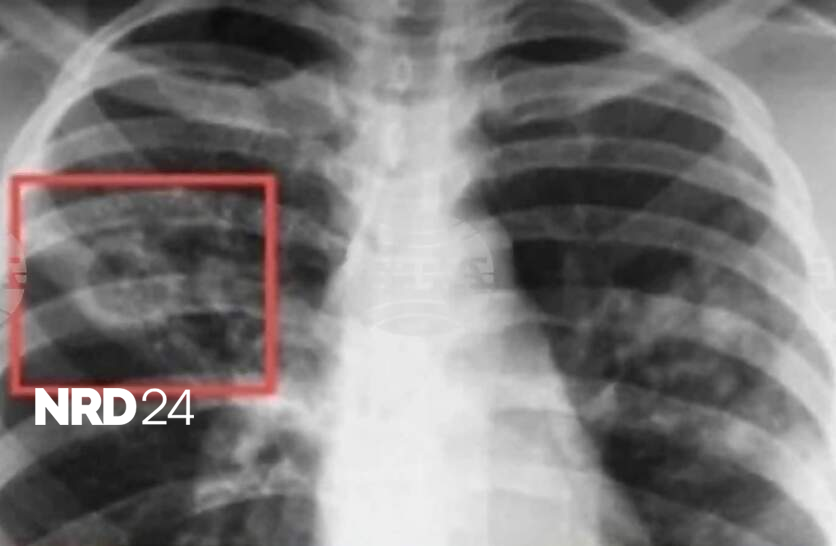

Започва Седмица на отворените врати за туберкулоза. Това съобщават на сайта си от Столичната регионална здравна инспекция (СРЗИ). Днес се отбелязва Световният ден за борба с туберкулозата. Инициативата е в рамките на изпълнението на Националната програма за превенция и контрол на туберкулозата в България, а целта е да се повиши обществената информираност по отношение на заболяването. До 27 март 2026 г., в Кабинета за анонимно, безплатно консултиране и изследване за ХИВ/СПИН (КАБКИС) ще бъдат предоставяни здравно-информационни материали, насочени към превенция на туберкулозата, както и безплатни консултации за начините на предаване на болестта, симптомите, възможностите за профилактика и значението на ранната диагностика. Кабинетът се намира в сградата на СРЗИ - ул. „Враня“ 20, ет. 5, стая 520, посочват от инспекцията. От СРЗИ призовават гражданите да се възползват от предоставените възможности за консултация като част от общите усилия за ограничаване на разпространението на туберкулозата. В България диагностиката, лечението и профилактиката на туберкулозата са безплатни за всички, които се нуждаят, независимо от техния здравноосигурителен статус, посочват на сайта си от Националния център по заразни и паразитни болести. По инициатива на Световната здравна организация, всяка година на 24 март се отбелязва Световният ден за борба с туберкулозата. Това е възможност за повишаване на осведомеността на населението за тежестта на болестта в национален и световен мащаб и за подобряване на усилията за грижа и превенция. Датата е избрана в чест на първото научно съобщение, направено от д-р Робърт Кох, който на 24 март 1882 г. обявява, че е открил причинителя на туберкулозата - бактерията Mycobacterium tuberculosis. Издръжливостта на туберкулозните бактерии във външната среда е много висока, посочват от онлайн платформата "Плюс мен", създадена от Министерството на здравеопазването (МЗ) с цел популяризиране на ваксините и ползите от тях. В жилищни помещения, върху различни предмети запазват инфекциозните си свойства повече от три месеца. Основният начин на предаване на причинителят на туберкулозата е при говор, издишване, кихане, кашляне. Поради високата издържливост на туберкулозните бактерии във външната среда е възможно те да се отделят с храчки, да изсъхват и във вид на вторичен аерозол да бъдат вдишани. В редки случаи причинителят на туберкулозата се предава и при консумация на заразена храна, най-често при консумация на заразено мляко. Министерството на здравеопазването провежда дългогодишна политика по профилактика на туберкулоза. От 1951 г. в страната ни е въведена задължителна ваксинация срещу болестта. Изпълнява се и национална програма за превенция и контрол на туберкулозата, чрез която се осигурява лечение на пациентите и наблюдение и профилактика на техните контактни лица, посочват още от "Плюс мен". През януари 2026 г. на сайта на МЗ за едномесечно обществено обсъждане беше публикуван проектът на Национална програма за превенция на туберкулозата в Република България 2026-2030 г. Във финансовия план към проекта на програмата са предвидени 4 440 100 млн. евро, които ще бъдат осигурени от бюджета на МЗ.